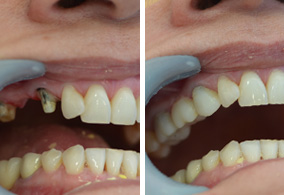

Replace teeth that have been lost with the passage of the years restoring functionality and aesthetics to your mouth.A dental implant is a cylinder shaped dental root manufactured alloplastic material (usually titanium) which is surgically implanted under the gums inside the maxillary or mandibular bone; once placed and osseointegrated, the dentist will place upon them crowns or fixed bridges that will replace the teeth lost, then the implant helps us provide retention and support a fixed or removable dental prosthesis.

Is a procedure that allows to recover the missing parts in a single session, in which dental implants are placed and are rehabilitated with their prostheses, are very few cases in which this procedure is indicated, once received this treatment is very important to note a soft diet.

The Dental implant merges with the bone of the jaw thus creating a stable support for the fake teeth, dentures, bridges and individual crowns placed upon implants will not move inside the mouth, providing comfort and safety when it comes to chewing and speaking.